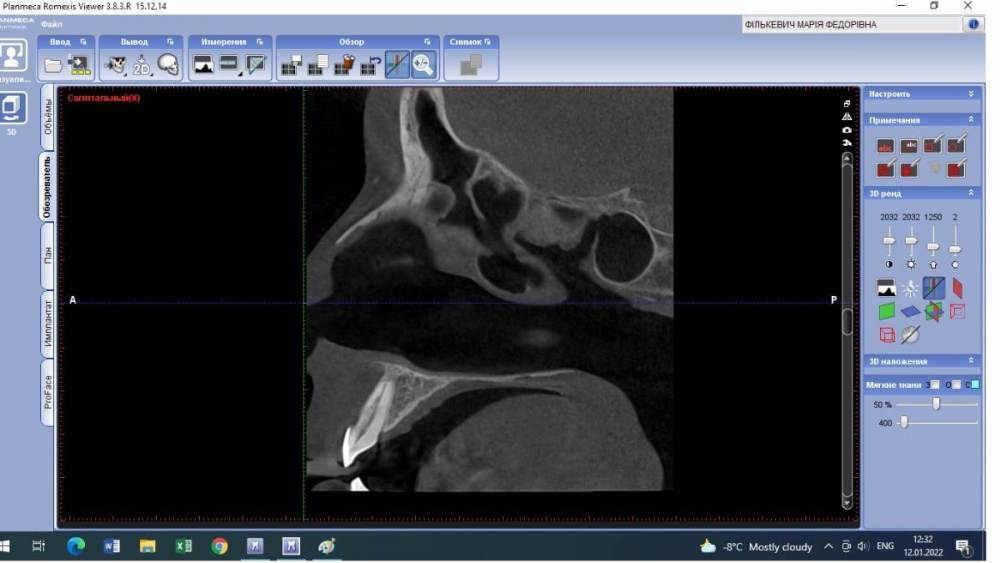

Lyubanya Опубликовано 12 января, 2022 Поделиться Опубликовано 12 января, 2022 Здравствуйте, коллеги. Вот такой случай. 11 зуб, пациентка 1963 г.р. Найдено случайно на КТ, делала его 3.09.21 по другому поводу, я взяла посмотреть для эндо премоляров. Визуально во рту вижу легкую розоватость пришеечно, и есть место, где цепляет зонд. Вопросов много. Каков точный диагноз? И что делать с этим зубом? Есть ли у него шансы пожить еще? Я так понимаю по возможности делается эндо в таком зубе. Если есть шансы то какова тактика? Ссылка на комментарий

Lyubanya Опубликовано 15 января, 2022 Автор Поделиться Опубликовано 15 января, 2022 9 часов назад, Александр23712 сказал: @Lyubanya Лично я бы, если не беспокоит, пока не трогал, но пациентку бы предупредил и кт показал. Может она ничего и не поймет, зато, когда/если заболит, придет к вам. Процесс прямо чуть ниже шейки. Как я понимаю, чтобы такое лечить, вам надо сначала лоскут откинуть, дальше в зависимости от кортикальной пластинки. Но у композита к дентину спорная адгезия ? . По поводу эндо не представляю, зачем депульпировать зуб раньше срока. Сделайте прицельный еще в 2 проекциях, интересно посмотреть Какая конкретно это резорбция? Разряжение вокруг основного канала = внутренняя резорбция корня? Или нет? Просто пыталась найти инфо, и нашла что внутренние это эндо. Но если можно наблюдать, то я только за) Пациентка работает у нас санитарочкой и я совсем не хочу ей лишнего стресса и тем более потери зуба. Хотела с главврачом обсудить, но пожалуй пока не буду. У меня на КТ нашлось новообразование, он ходил давил что надо удалить зуб вместе с ним. В итоге спустя полгода оказалось, что это цементно-костная дисплазия и ничего удалять не нужно. Спасибо Рогацкину.? И как мне сделать две проекции на пленочном?? 9 часов назад, Дмитрий Л. сказал: Реставрация без эндо; риск рецессии. Имеете ввиду перекрыть то место, где зонд цепляется? Ссылка на комментарий

Дмитрий Л. Опубликовано 15 января, 2022 Поделиться Опубликовано 15 января, 2022 Это инвазивная цервикальная резорбция, связи с пульпой нету, хирургически можно откинуть лоскут и реставрировать. Риск рецессии. Другое лечение - выжидание, риски прогресса с потерей зуба, смотрите на возраст пациента. 1 Ссылка на комментарий

Lyubanya Опубликовано 16 января, 2022 Автор Поделиться Опубликовано 16 января, 2022 8 часов назад, Дмитрий Л. сказал: Это инвазивная цервикальная резорбция, связи с пульпой нету, хирургически можно откинуть лоскут и реставрировать. Риск рецессии. Другое лечение - выжидание, риски прогресса с потерей зуба, смотрите на возраст пациента. А вот размытость дентина вокруг хода канала, это она же? Думала насчет лоскута, но я так понимаю поможет он не особо, там альвеола уже.? Ссылка на комментарий